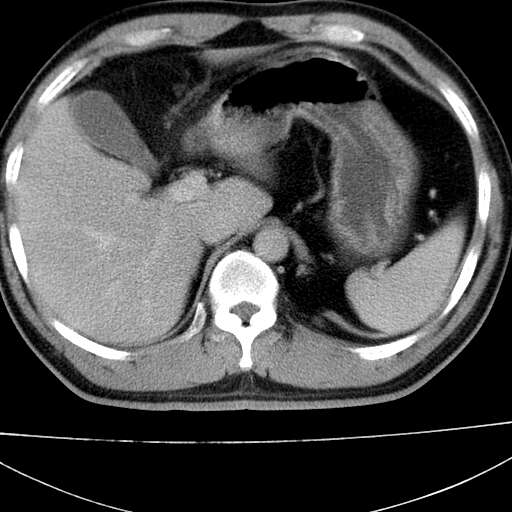

标题: CT21921:腹膜后腔肿物。患者男39Y。体检。增强扫描时间欠准

左肋隔角占位,考虑胸膜间皮瘤

1)考虑左肺下叶后基底段(或左下胸后壁胸膜)软组织团块,性质待定;建议行进一步检查。2)左肾结石。

左膈肌角后腹膜腔见肿物影,其内见脂肪密度灶及软组织密度灶,强化不明显。病灶大部在后腹膜内。考虑异位嗜铬细胞瘤或脂肪肉瘤、畸胎瘤

左下肺隔离症,可见从胸主动脉发出异常血管供应